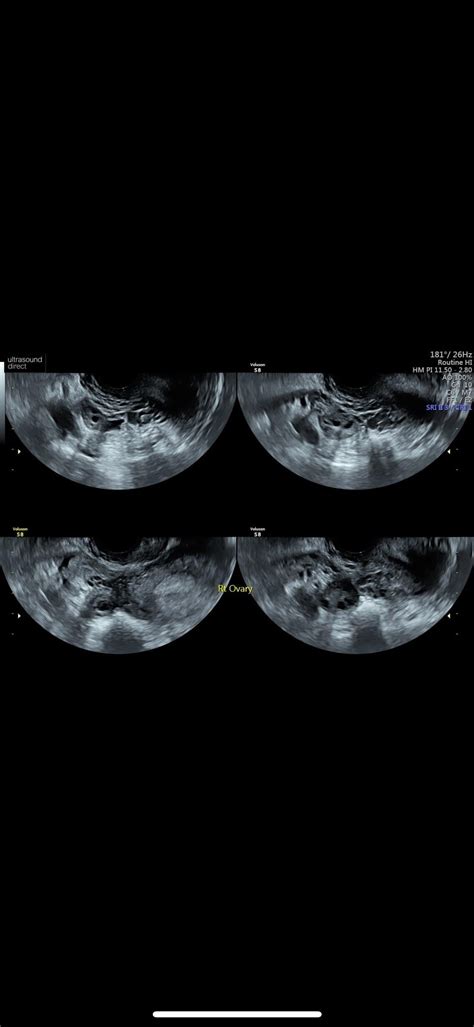

Okay, first things first, let’s talk about what the 20-week scan actually is. This isn’t just a fun sneak peek at your baby (though, let’s be honest, that’s a major perk!). The 20-week scan is a crucial medical appointment that provides a detailed look at your baby’s development. It’s a comprehensive ultrasound examination that typically takes place between 18 and 21 weeks of pregnancy. The main goal? To assess your baby’s physical development and identify any potential abnormalities. During the scan, the sonographer will check everything from the baby’s brain and spine to their heart, kidneys, and limbs. They’re essentially doing a full body check-up while your little one is still cozy inside! It’s also a chance to confirm the baby’s sex, if you want to know, and to check the position of the placenta. This scan is really thorough, and it’s designed to give you and your healthcare team as much information as possible about your baby’s health. Now, I know, hearing about all the things they check can sound a bit scary, but remember, the vast majority of scans come back with good news. Think of it as a super-detailed health check to ensure everything is progressing as it should. It’s a proactive step in ensuring the well-being of both you and your baby.